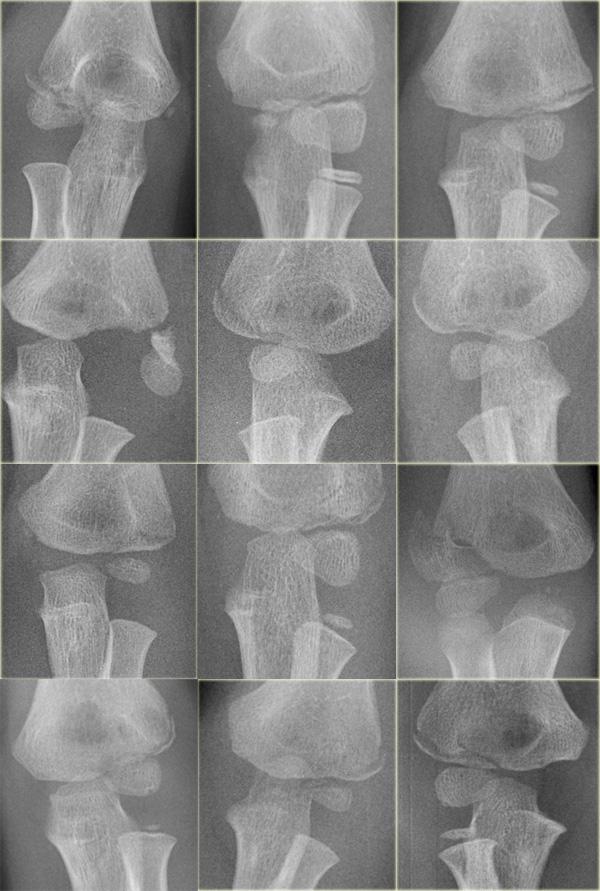

Gãy lồi cầu ngoài (7).

Bên trái là một vài ví dụ về gãy lồi cầu ngoài.